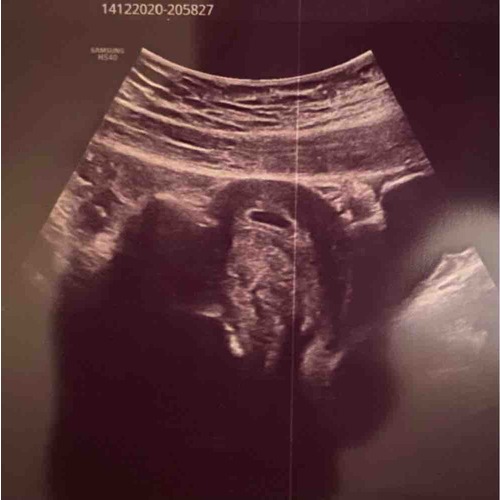

Ja, ik heb dit ook gehad bij 5+3. Wat ook klopte Volgens mijn eigen berekening. Toen toch een echo laten maken en dat valt dan toch wel even tegen om "niks" te zien. Ik heb toen 10 dagen later weer een echo gehad en toen was er een mooi vruchtje te zien met hartslag! 😊 inmiddels alweer 11+2 en alles gaat nogsteeds goed!

Ik was ook twee weken korter zwanger dan zelf berekend. 6.2 ipv 8. Wel een kloppend hartje gezien toen. Maar dus minder lang, en alles goed gekomen. Later ook niks aan de datum aangepast.. ik ben op schema blijven lopen met die 6.2.